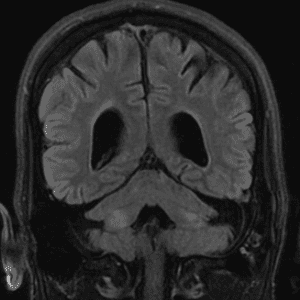

Neurodegenerative Diseases